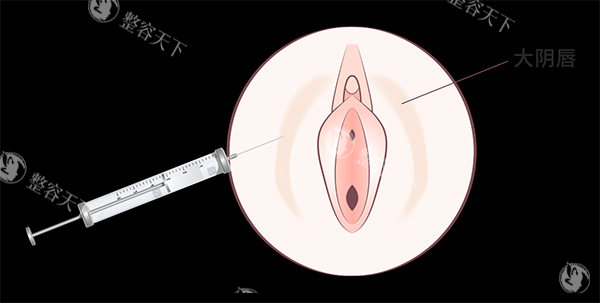

私密粉嫩手术,也被称为阴唇漂红术或私密部位色素沉着改善术,是一种通过医学手段改善女性私密部位颜色的美容整形手术。这种手术主要针对私密部位(如阴唇)颜色偏深、色素沉着等问题,通过激光或色素植入等方式,使私密部位颜色变得更加粉嫩,从而提升整体美观度。

纹绣漂红是通过专用的纹刺针将色料刺入真皮层,达到染色的结果。这种方法的优点是结果立竿见影,但缺点是改善期较长,对纹绣师的技术要求较高。此外,纹绣漂红使用的染料质量参差不齐,部分人可能会出现过敏反应。